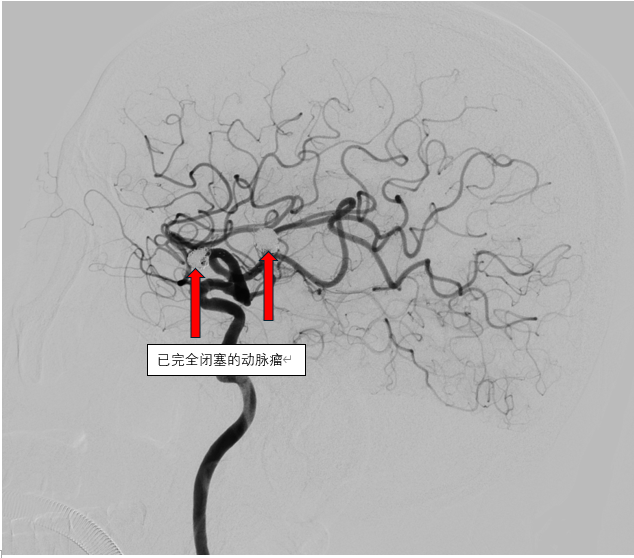

这是一场不容有失的“微雕”手术。在高精度数字减影血管造影的引导下,在介入导管室的密切配合下,介入团队犹如拥有“透视眼”,将微导管如丝般柔顺地导航至病灶处。随后,比发丝还细的铂金弹簧圈被精准、稳定地送入动脉瘤囊内,直到将那个致命的膨出部位完全填塞,血流不再涌入,破裂风险被彻底解除。手术台上,危机化解;监护室里,生命体征渐趋平稳。从命悬一线到转危为安,再到最终好转出院,这场与死神的极速竞赛,彰显了医院在急诊脑血管介入救治方面的强大实力与高效协作。

信任,是医患之间最宝贵的桥梁。一个月前,另一位患者在住院期间被查出颅内竟藏有三枚“不定时炸弹”——三个高危动脉瘤。面对如此复杂的病情,神经内科团队没有冒进,而是制定了审慎而周密的“分步拆弹”计划。首次手术,马磊主任带领团队凭借丰富的经验,成功栓塞了其中风险最高的两个动脉瘤。术后患者恢复良好,病情平稳。这份成功的体验和期间无微不至的关怀,铸就了患者及家属坚实的信任。基于此,患者本月再次满怀信心地入院,接受最后一枚动脉瘤的栓塞治疗。手术台上,团队操作愈发沉稳精准,顺利完成“收官之战”。术后患者同样病情平稳,好转出院。